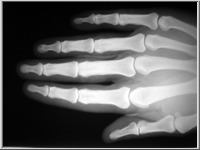

A képekre kattintva a röntgenfelvételek üveglemezeinek reprodukcióit, a kis képek jobb felső sarka melletti ikonokra klikkelve pedig az üveglemezeket védő, Gothard által feliratozott, a felvételek adatait tartalmazó borítékok reprodukcióit láthatjuk.

Az 1. sorszámú lemez elveszett, csak papírmásolat maradt fenn róla. A 25. és 26. sorszámú borítékok 2-2 felvételt tartalmaznak (itt a-val és b-vel jelölve), míg a 32. sorszámú lemez eltört, két darabban van.